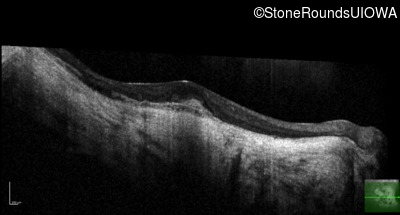

Optical Coherence Tomography - Right - 20/100 -2

Exemplar / OCT Stack

OCT Stack